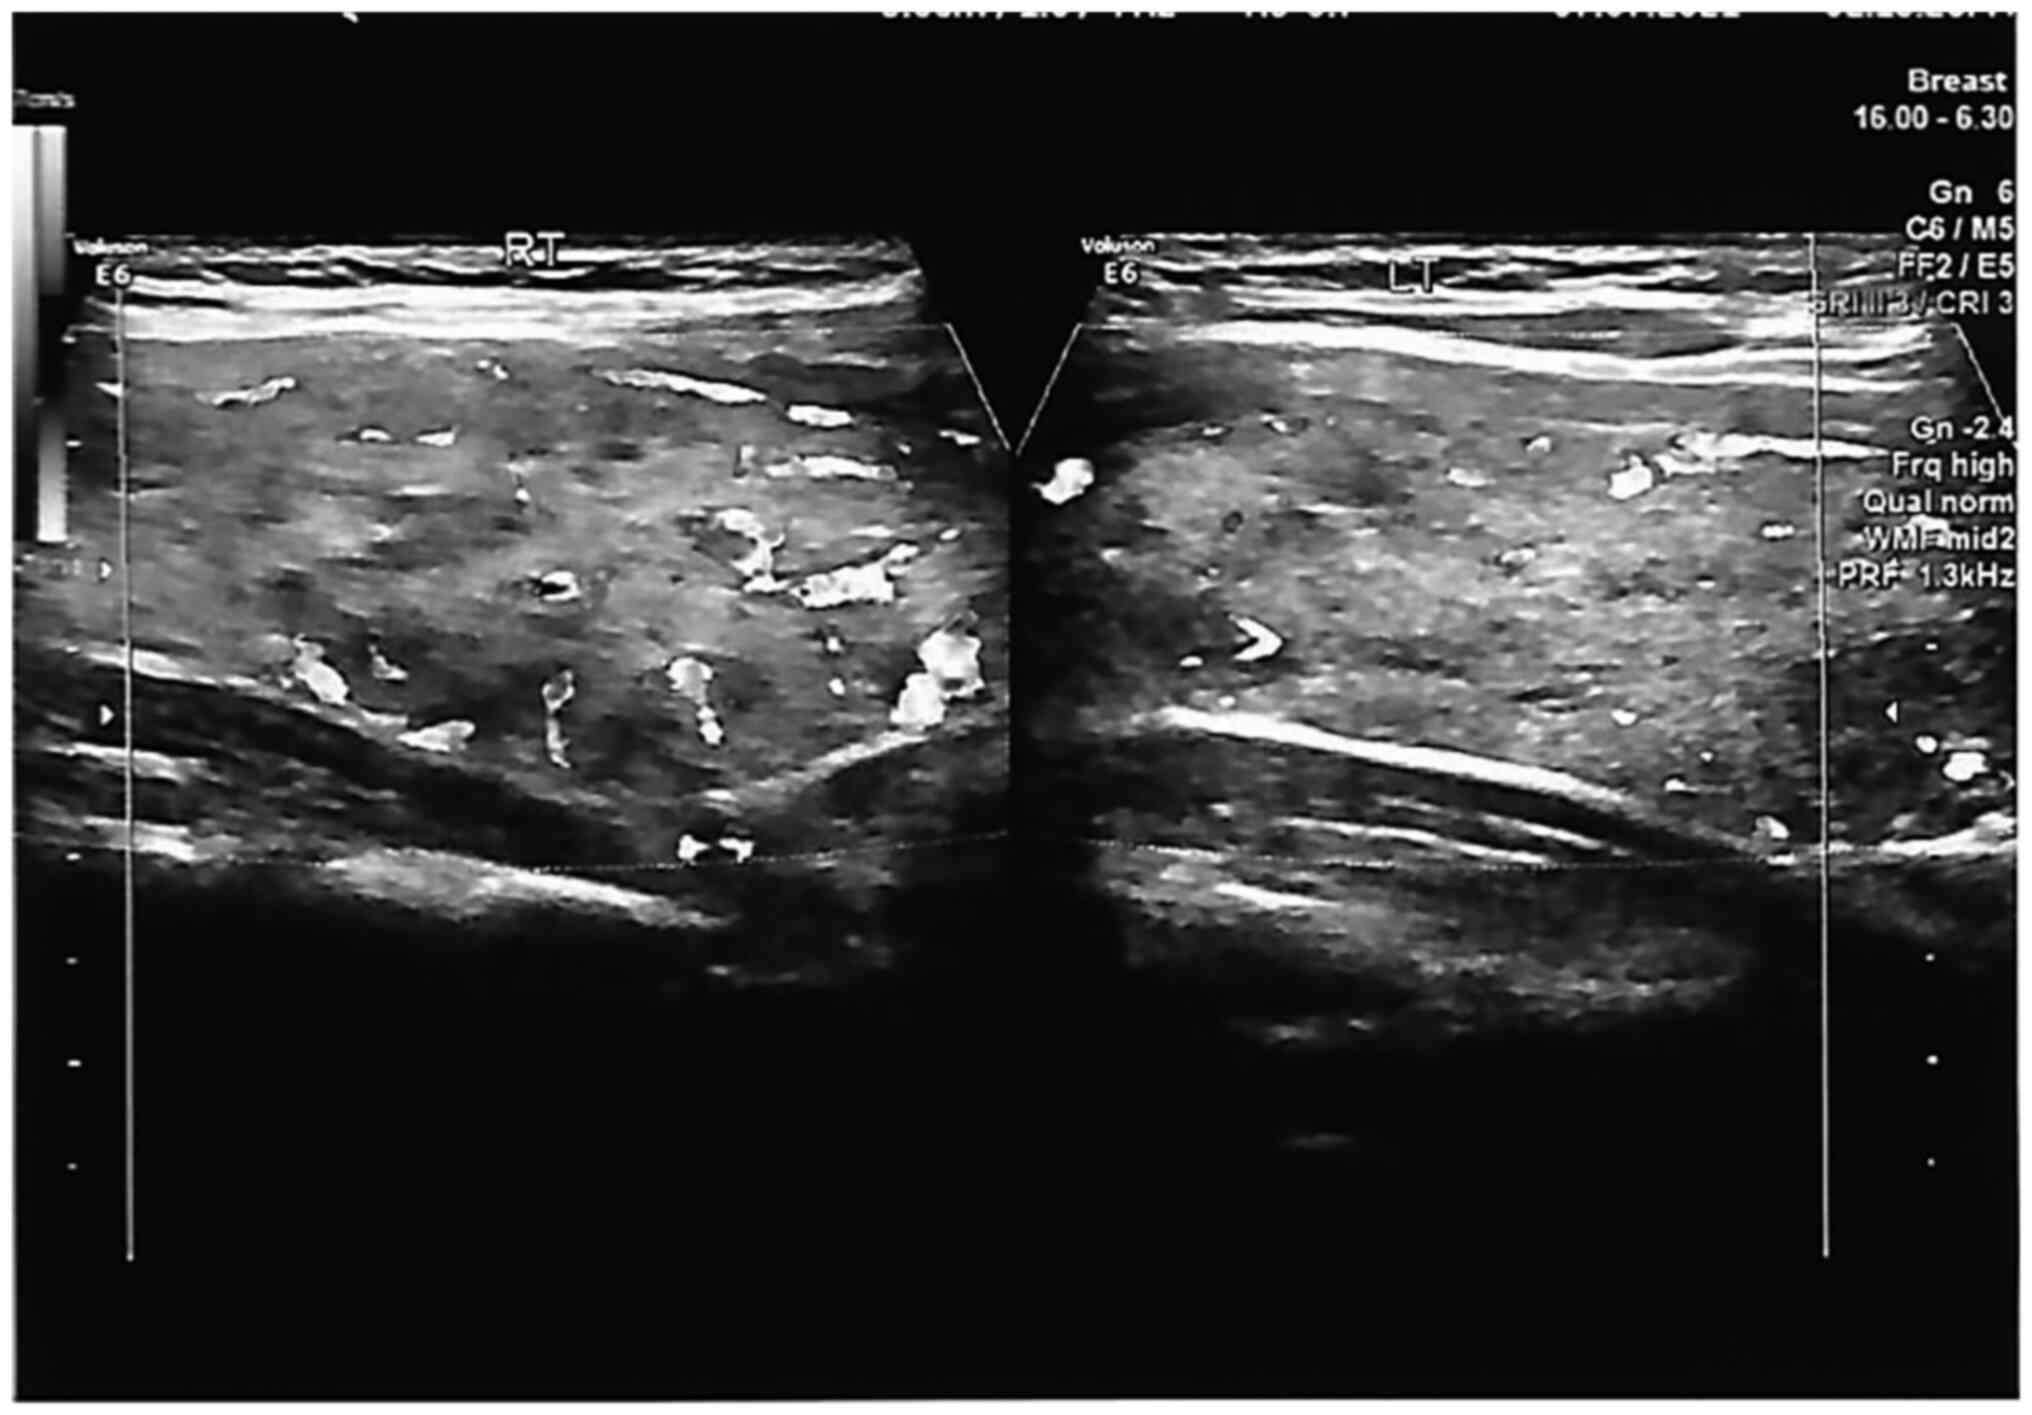

0.0-35.0 IU/ml). A thyroid ultrasound revealed a mildly enlarged

goitre with increased vascularity (Fig.

1 and Table II). Blood count,

| Table IIThyroid ultrasound report. |

Table II

Thyroid ultrasound report.

| Thyroid ultrasound

characteristic | Description |

|---|

| Findings | The thyroid gland is

mildly enlarged and heterogeneous with diffusely increased

vascularity. The thyroid gland was larger than usual |

| | No retrosternal

extension or tracheal deviation |

| | The right lobe

measures 2.4x1.9x6.8 cm |

| | The left lobe

measures 2.4x2.4x6.8 cm |

| | The isthmus measures

0.4 cm AP |

| | There are bilateral,

small well-circumscribed, benign-appearing, hypoechoic thyroid

nodules measuring up to 0.8 cm with no dominant nodule on either

side |

| | Small reactive

anterior cervical lymph nodes were noted, measuring up to 0.3

cm |

| Impression | Moderately-enlarged

thyroid (larger than usual), with multiple well-defined, hypoechoic

nodules measuring up to 0.8 cm and diffusely increased vascularity.

These appearances are suggestive of Graves' disease |